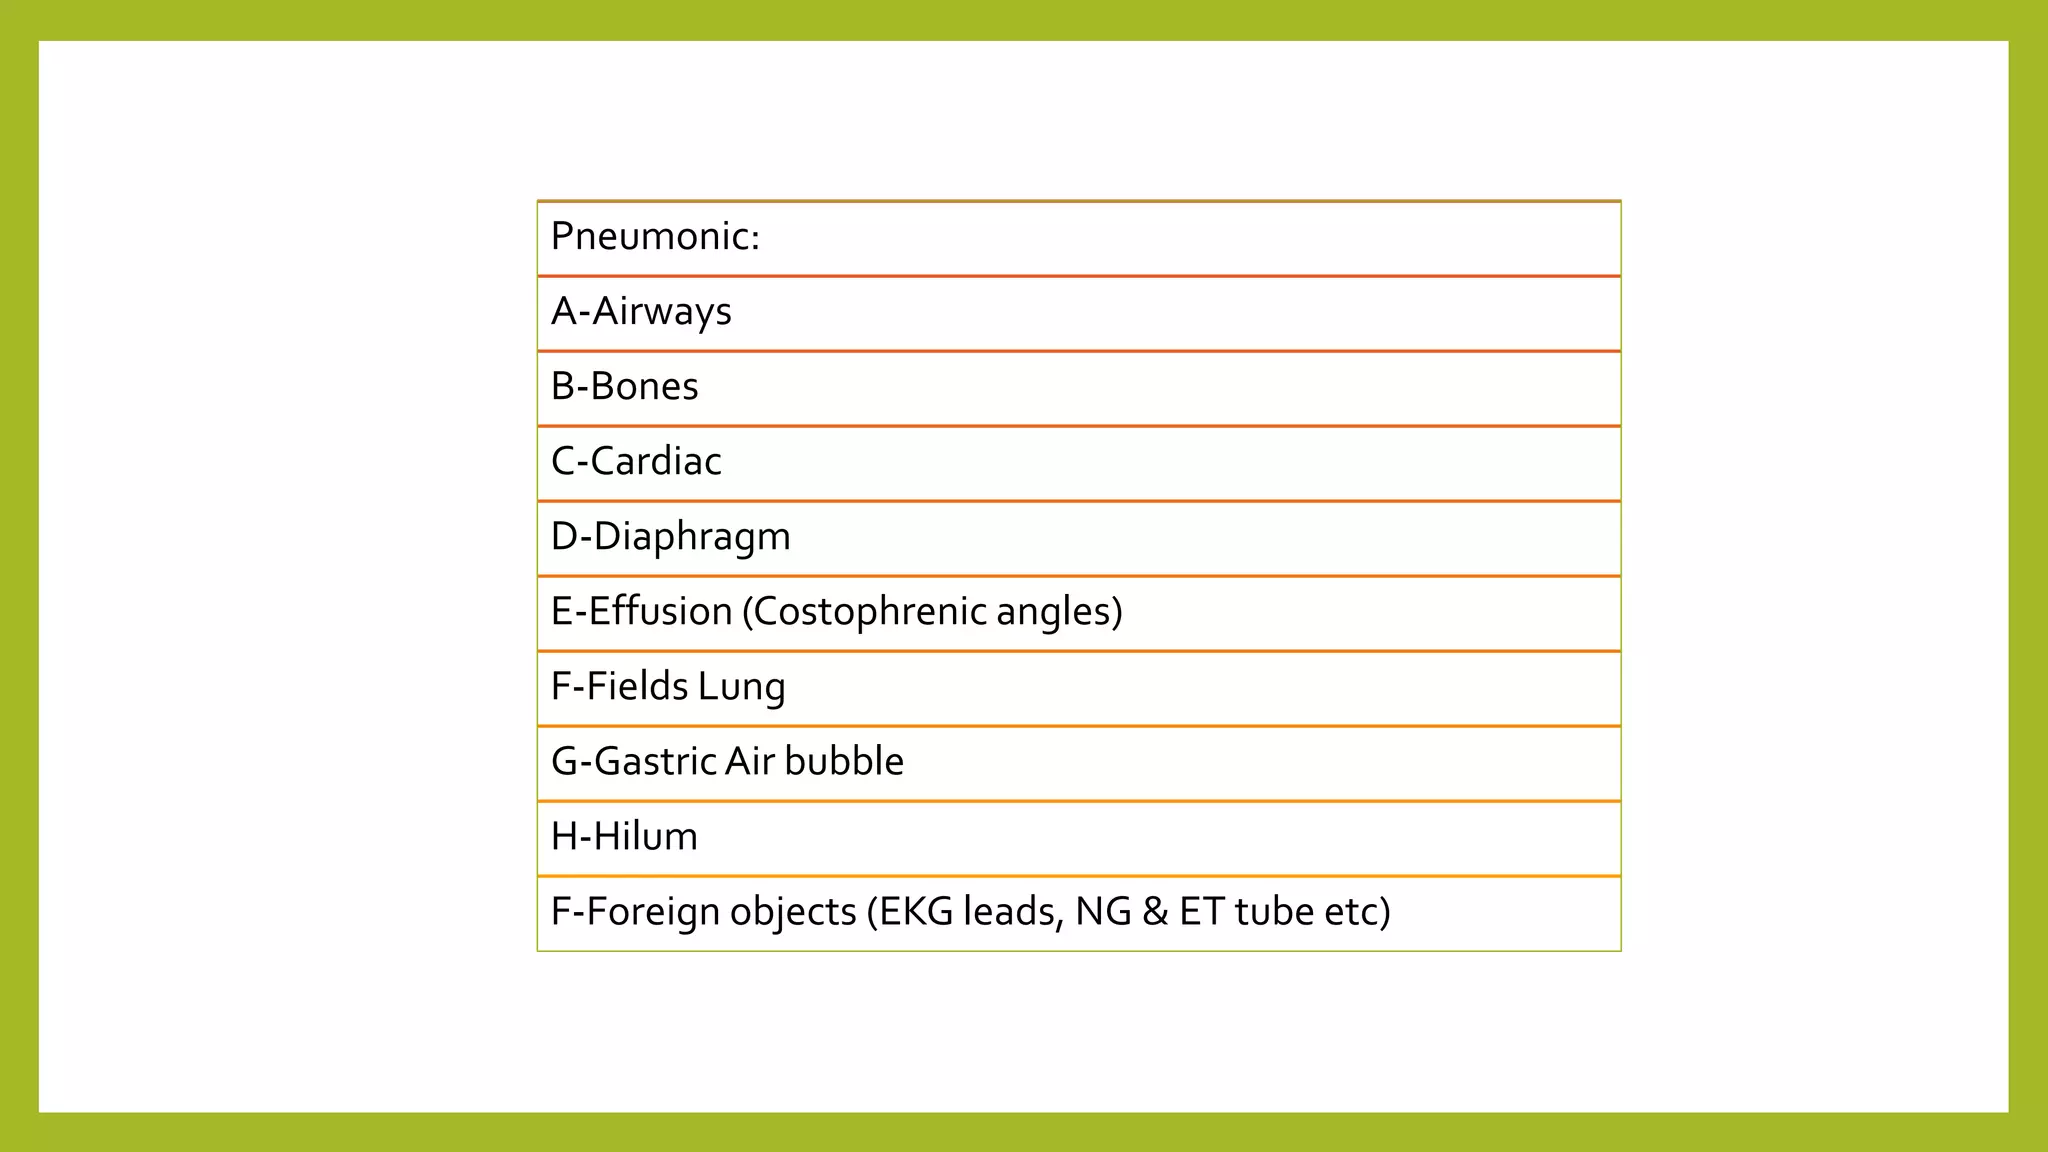

The document provides guidance on approaching and interpreting chest x-rays (CXR). It outlines steps to check the name, date and quality of the film, systematically scan the CXR looking for abnormalities, and determine if the lungs appear too white or black. Specific signs are described to help localize abnormalities, including the cardiac silhouette sign and pleural effusion signs. Examples are given of respiratory distress syndrome, tetralogy of fallot, transposition of great arteries, and total anomalous pulmonary venous return. The take home message is to summarize positive findings, compare to prior CXRs if available, and confirm findings with a radiologist.